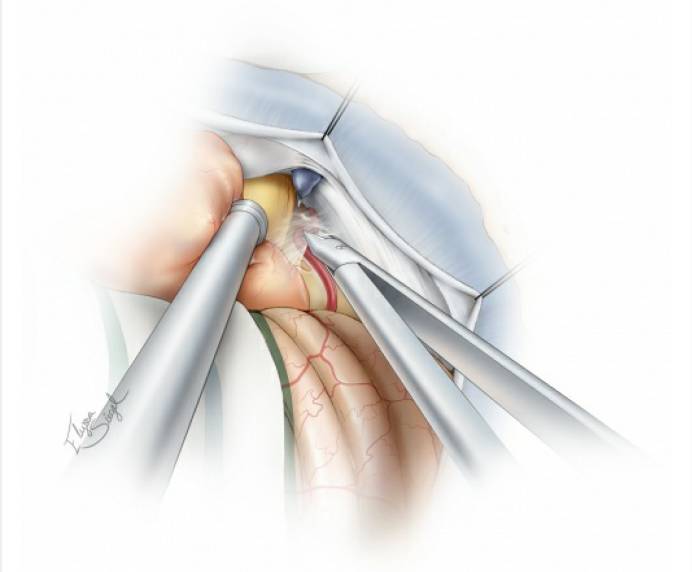

图4. 硬膜下初步暴露位于左侧的肿瘤。注意图中所示:去除乙状窦表面的骨质后,可以用缝线沿乙状窦边缘悬吊,将乙状窦牵开,获得更好的手术视野(扩大乙状窦后入路。译者注)。如果没有预置腰大池引流,则可通过打开后组颅神经周围的脑池释放脑脊液。随后,分离肿瘤后缘与小脑表面的蛛网膜粘连。

图5. 显示颅神经的大致分布与内听道后型肿瘤前缘包膜的关系。术前仔细研究MRI可使术者形成对肿瘤病理解剖以及重要解剖结构部位的立体构象。

图6. 接下来,电凝并阻断肿瘤后包膜的血管。注意保护供应小脑的过路动脉。

图7. 下一个重要的步骤是阻断肿瘤基底血供,沿着岩尖外侧逐步阻断供血动脉。笔者会沿着这个界面尽可能地分离肿瘤,但是需特别注意避免损伤肿瘤前包膜与颅底之间出入相应骨孔的颅神经。此时,适当释放脑脊液可使肿瘤轻微移动以避免对周围结构的过度牵拉。随后,暴露岩骨-天幕连接处,这是手术的方向标。对于中型肿瘤,沿着肿瘤下极可见到后组颅神经。